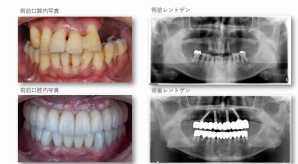

¥¤¥ó¥¹¥¿¥°¥é¥à¤ËºÜ¤»¤Æ¤¤¤ëÅö±¡¤Î¾ÉÎã¤Ç¤¹

ðÌî»õ²Ê¾ÉÎ㢠ÀèÅ··ç»¶ºÀµ¥¤¥ó¥×¥é¥ó¥È

ðÌî»õ²Ê¾ÉÎã¡¶ºÀµ¥¤¥ó¥×¥é¥ó¥È¥»¥é¥ß¥Ã¥¯